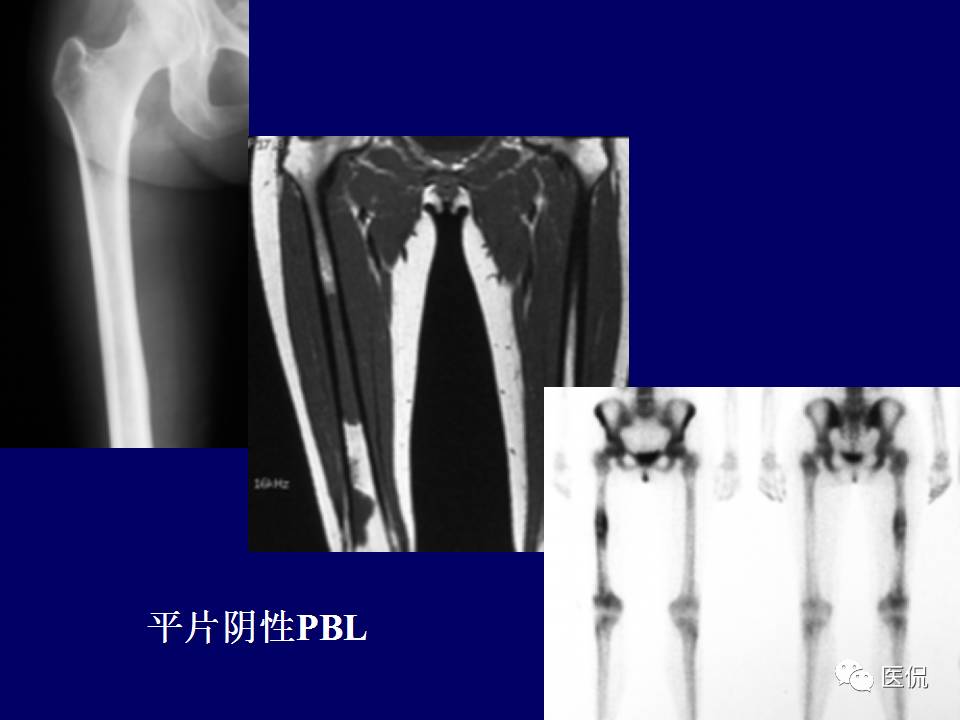

原发性骨淋巴瘤,是一种少见肿瘤。平片上干骺端单发、浸润性骨质破坏、层状骨膜反应+MR上骨髓侵犯、软组织肿块+年龄>30岁均可高度提示,影像学区分原发和继发PBL比较困难。更多知识,请往下看~